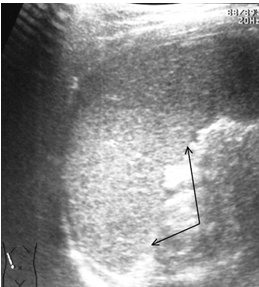

Ушибы селезенки сопровождаются интерстициальным отеком и геморрагическим пропитыванием тканей. Прямыми эхографическими признаками в первые 3–5 часов после травмы являются снижение эхогенности паренхимы и четкости контура органа, а также «разреженность» эхоструктуры паренхимы. Геморрагическое пропитывание паренхимы манифестировало наличием гиперэхогенных зон с нечеткими размытыми контурами в области повреждения (рис. 1). Характерно увеличение размеров всей селезенки или преимущественно поврежденного сегмента с нарушением ее конфигурации. Результаты цветового допплеровского картирования свидетельствуют о снижении кровотока, степень которого коррелирует с выраженностью эхографических проявлений отека паренхимы.

Рис. 1. Ушиб селезенки. Зона геморрагического пропитывания указана стрелками.